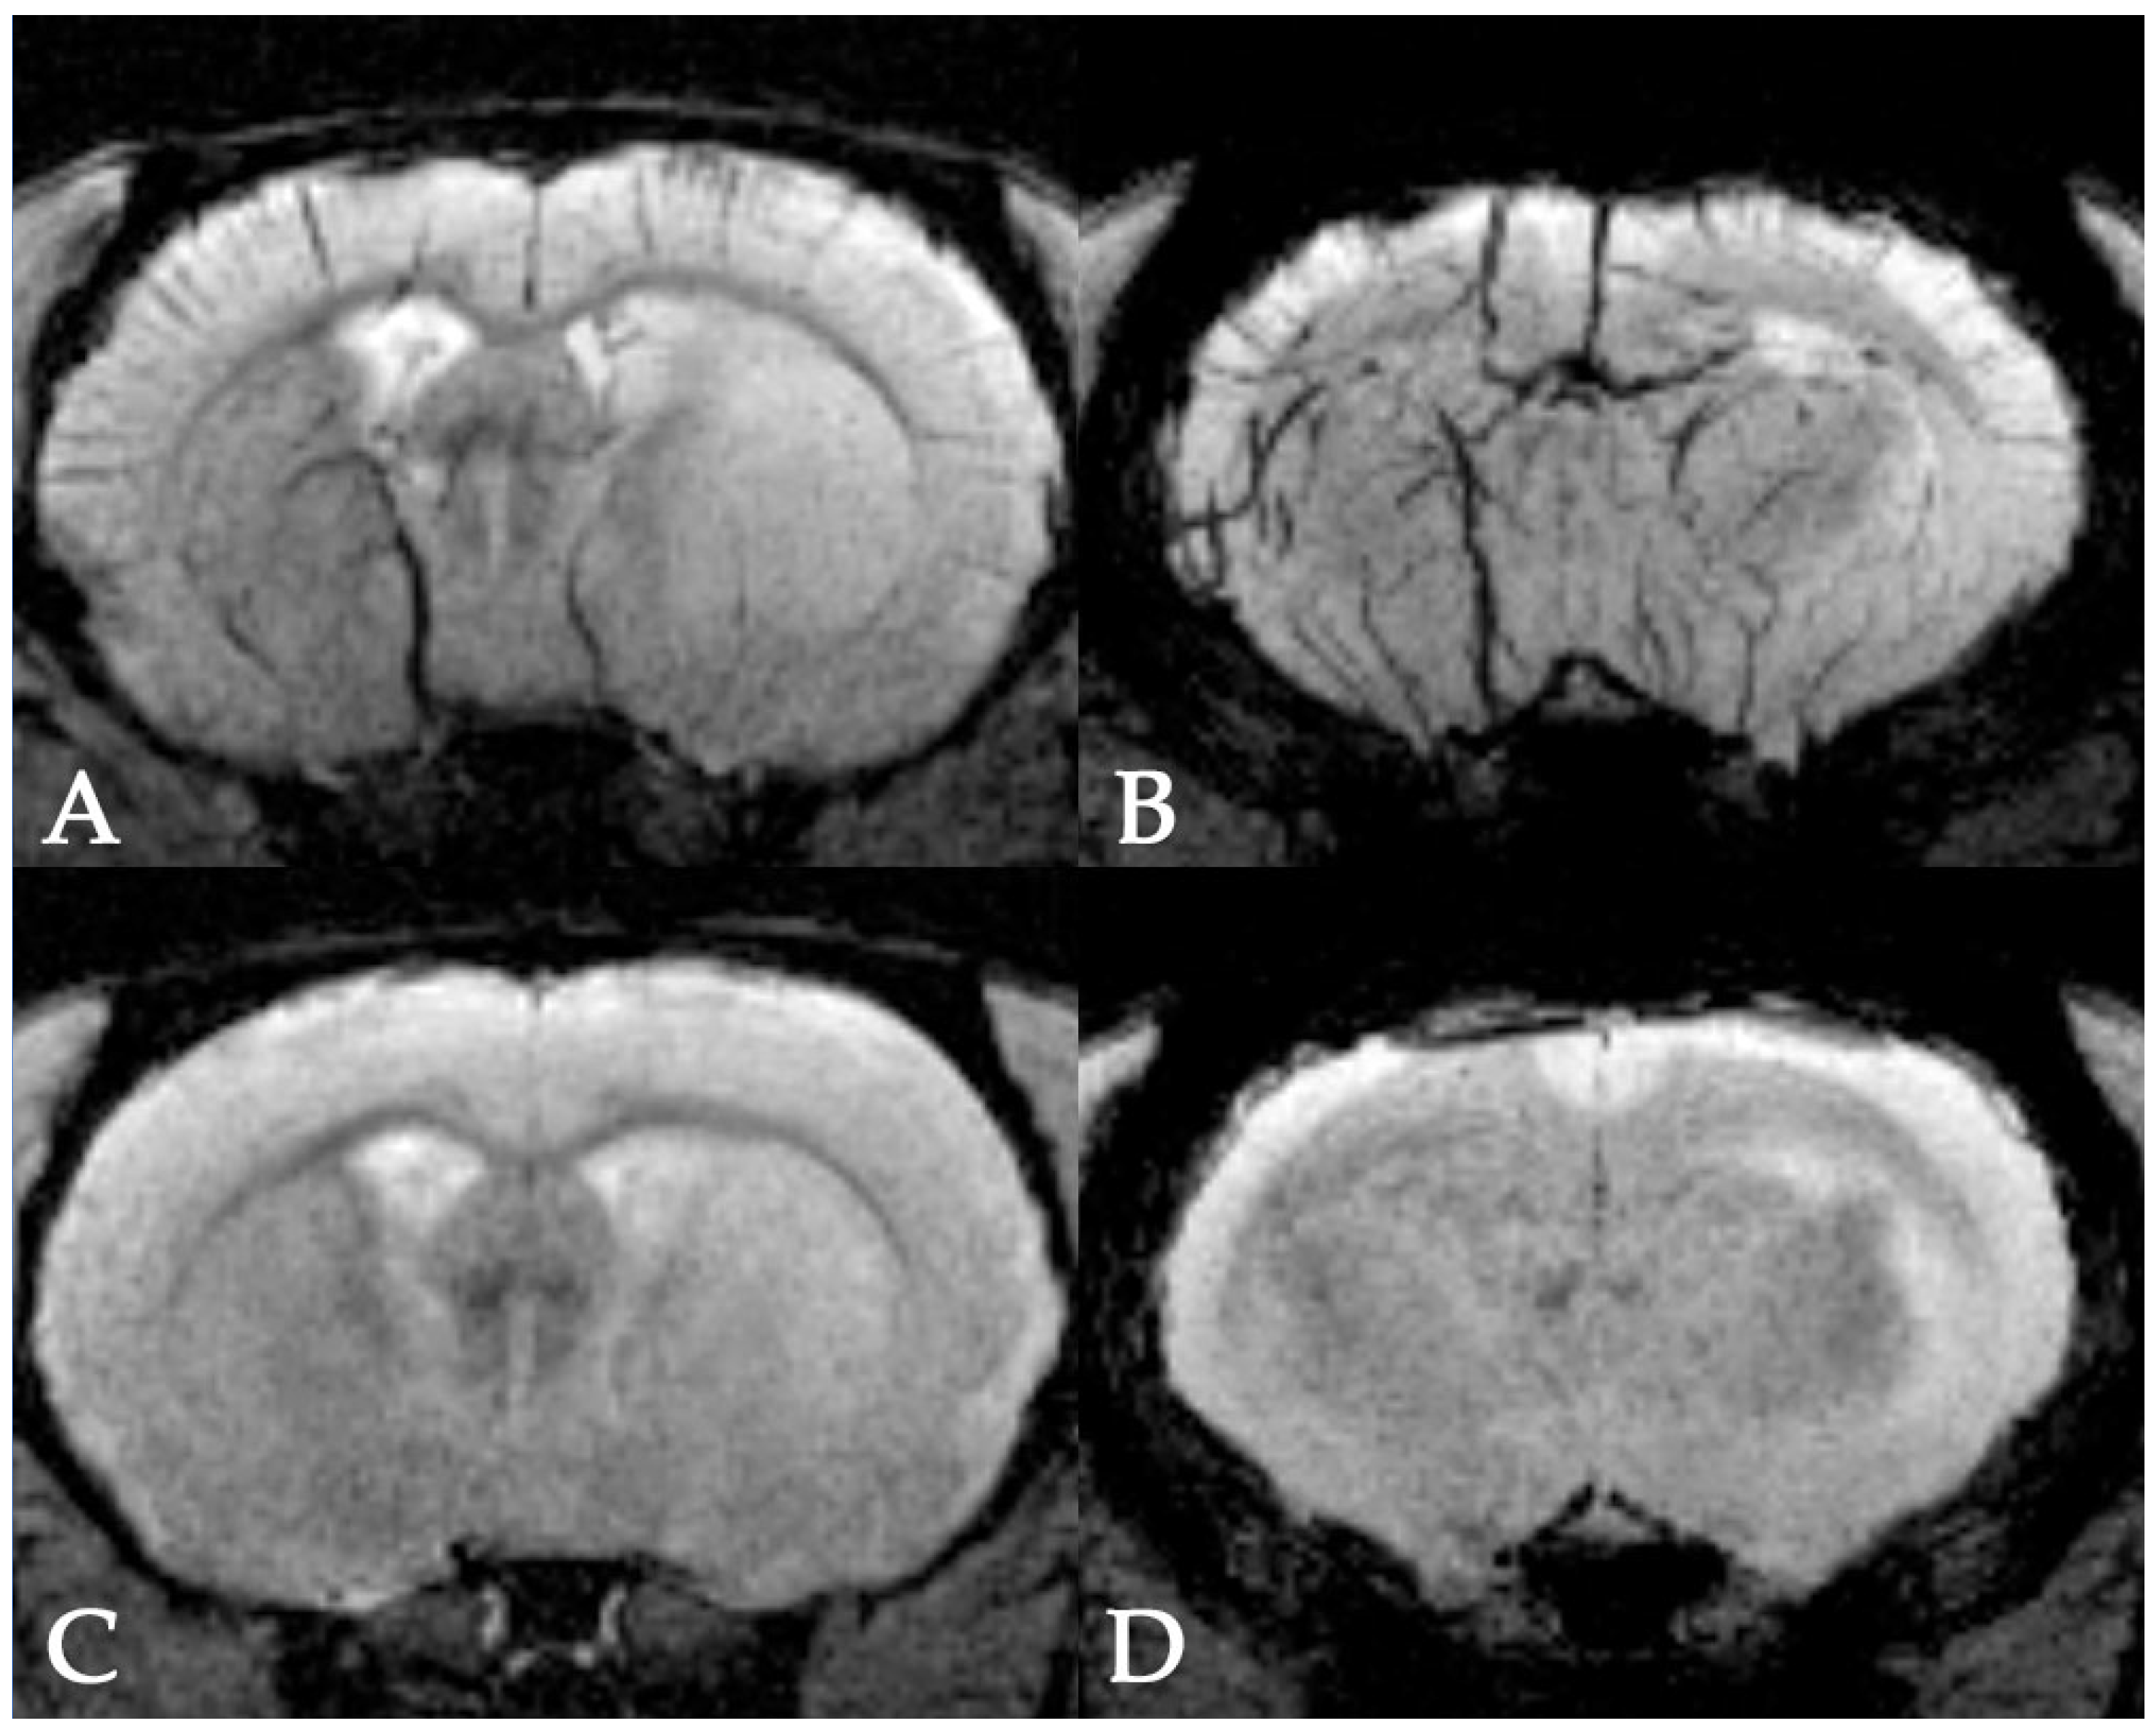

2.7. Magnetic Resonance Imaging

- Gubskiy, I.L.; Namestnikova, D.D.; Cherkashova, E.A.; Chekhonin, V.P.; Baklaushev, V.P.; Gubsky, L.V.; Yarygin, K.N. MRI Guiding of the Middle Cerebral Artery Occlusion in Rats Aimed to Improve Stroke Modeling. Transl. Stroke Res. 2018, 9, 417–425. [Google Scholar] [CrossRef]

- Salikhova, D.; Bukharova, T.; Cherkashova, E.; Namestnikova, D.; Leonov, G.; Nikitina, M.; Gubskiy, I.; Akopyan, G.; Elchaninov, A.; Midiber, K.; et al. Therapeutic effects of hipsc-derived glial and neuronal progenitor cells-conditioned medium in experimental ischemic stroke in rats. Int. J. Mol. Sci. 2021, 22, 4694. [Google Scholar] [CrossRef]